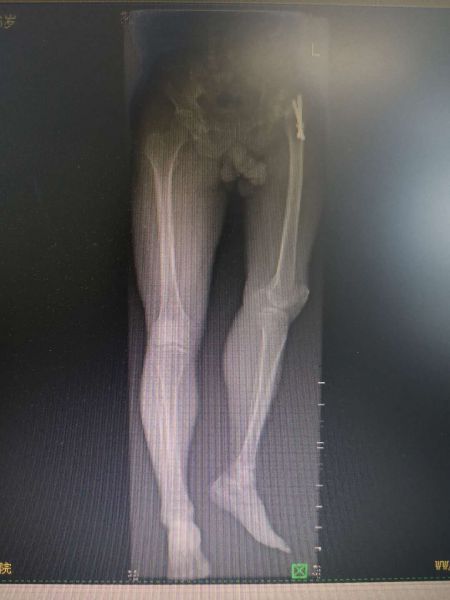

患者慕名找到湘西州人民医院骨一科主任赵峻主任医师,希望通过赵峻主任医师的治疗,能够自由行走,不再受疼痛的困扰。赵峻主任医师带领其团队,对患者进行仔细的体格检查,并仔细阅读了患者的相关影像学资料,发现患者左髋关节活动度已完全尚失,左下肢明显外旋畸形,且左下肢较对侧短了近6cm。经赵峻主任医师及其团队讨论后,制定详细的手术方案。完善术前检查后,于4月19日在麻醉科及手术室共同协助下行左侧人工髋关节置换术,虽然术前已经对术中可能出现的困难进行了充分的准备,但手术的复杂程度远远超过预期。面对术中各种挑战,赵峻主任带领其团队,沉着应对,最终历时4个小时,顺利完成手术。术后行X线片检查提示患者左下肢长度较前明显恢复,且在骨一科全体医护人员的精心指导下积极行功能锻炼,患者左侧髋关节活动度明显改善。最终患者健康出院。

患者术前X线片 患者术后X线片